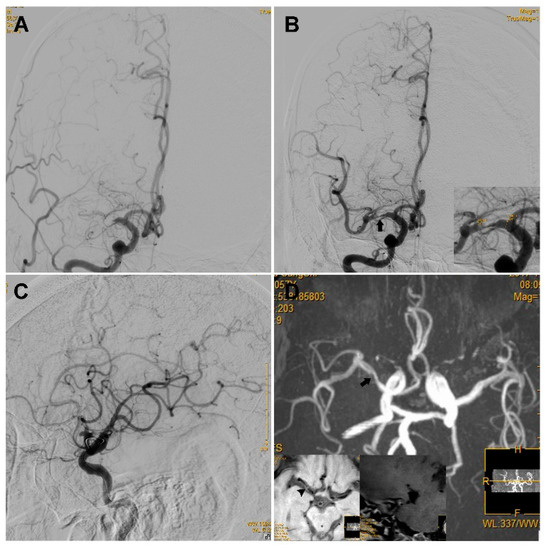

Sixty-one patients had mild to moderate residual stenosis (Group 1b), whereas 25 patients had severe residual stenosis (Group 2b, a typical case is illustrated in Figure 3). The two groups showed no significant difference regarding the reocclusion rate on follow-up angioplasty (0/61 vs. 2/25, p = 0.082). The two groups showed no significant difference in sICH (0/61 vs. 1/25, p = 0.298) or favorable functional outcome prognosis rate (41/61 vs. 16/25, p = 0.808, Table 2). The clinical and angiography characteristics of the three groups are summarized in Table 2.

Figure 3. An ICAS case with a high degree of residual stenosis. An elderly patient presented with left limb weakness for 16 h, and the NIHSS score was 14. (A) The first run of DSA showed occlusion of the right MCA. (B) The anterior–posterior view of DSA showed a high degree of stenosis (black arrow) located at the right MCA after one pass of stent retrieval and emergent angioplasty via a 2.0–15 mm Maverick balloon; as the figure on the bottom right shows, the residual stenosis was 81.2% according to the WASID criteria. (C) Lateral view of the DSA showed that reperfusion with an mTICI of ≥2b was achieved and it was maintained for more than 20 min. (D). TOF-MRA performed 6 days after the operation showed a high degree of stenosis in the right MCA (black arrow). The high-resolution MRI scan on the bottom left showed an eccentric plaque (arrowhead) with enhanced stenosis that was observed at the right MCA. ICAS, intracranial atherosclerosis; NIHSS, National Institutes of Health Stroke Scale; DSA, digital subtraction angiography; MCA, middle cerebral artery; mTICI, modified thrombolysis in cerebral infarction; TOF-MRA, time of flight for magnetic resonance angiography; MRI, magnetic resonance imaging.